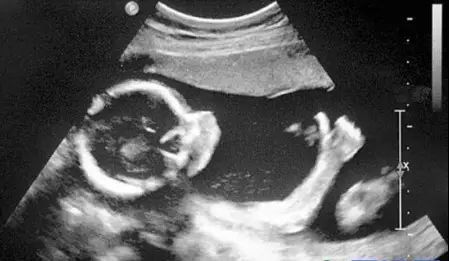

B超对于人体管腔的液体流动和腹腔脏器检查的敏感性较高,我们常常遇到的胆囊结石,肾结石,血管狭窄,心脏功能等等检查,都是B超的用武之地。B超有着独特的优势,便携,能够在床边,甚至在手术中使用。此外,B超市利用超声波成像,也没有所谓的辐射。所以孕妇多采用B超检查。